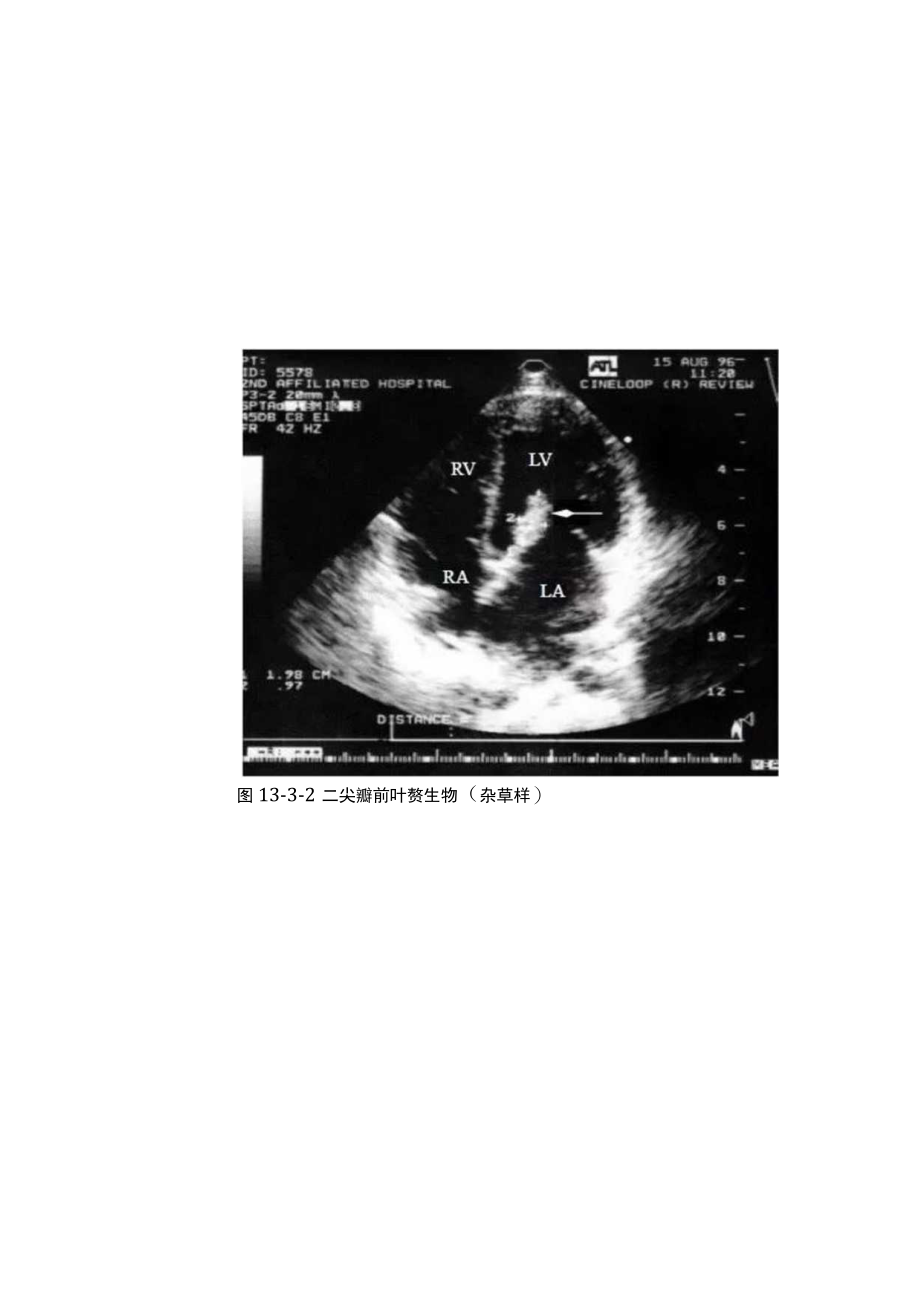

1、超声原创I感染性心内膜炎的七大超声心动图表现第3节超声心动图表现患者仰卧位或左侧卧位,取左心室长轴切面、心尖四腔心切面、二尖瓣水平左心室短轴切面、心底短轴切面、心尖五腔心切面和右心室流入道切面观察二尖瓣、主动脉瓣、三尖瓣和肺动脉瓣的形态与活动,仔细探查各瓣膜有无脱垂和赘生物,并注意异常血流冲击的内膜面、动脉壁上有无异常回声,用彩色多普勒显示瓣膜关闭不全的程度、观察反流的起始部位和喷射方向,然后再用频谱多普勒测量反流的速度。一、自然瓣膜感染性心内膜炎赘生物(1)瓣膜赘生物。瓣膜上单发或多发、呈等回声或强回声的米粒状、绿豆状或息肉状异常回声,以二尖瓣和主动脉瓣多见,而三尖瓣和肺动脉瓣较少见(图13

2、-3-1至图13-3-5)o图13-3-1二尖瓣赘生物(团块状)图13-3-2二尖瓣前叶赘生物(杂草样)图13-3-3二尖瓣多发性赘生物图13-3-4主动脉瓣赘生物图13-3-5三尖瓣赘生物可有蒂,能随瓣膜启闭而运动。(2)瓣膜外赘生物。当室间隔缺损时,在室间隔缺损的右心室面可显示呈息肉状的赘生物强回声(图13-3-6)。图13-3-6室间隔缺损时右心室面赘生物当动脉导管未闭时,在肺动脉内膜面和肺动脉瓣可显示大小不等的绿豆状、息肉状的赘生物强回声(图13-3-7和图13-3-8)o图13-3-7动脉导管未闭时肺动脉瓣赘生物图13-3-8动脉导管未闭时肺动脉外侧壁赘生物二尖瓣关闭不全时,于左心房